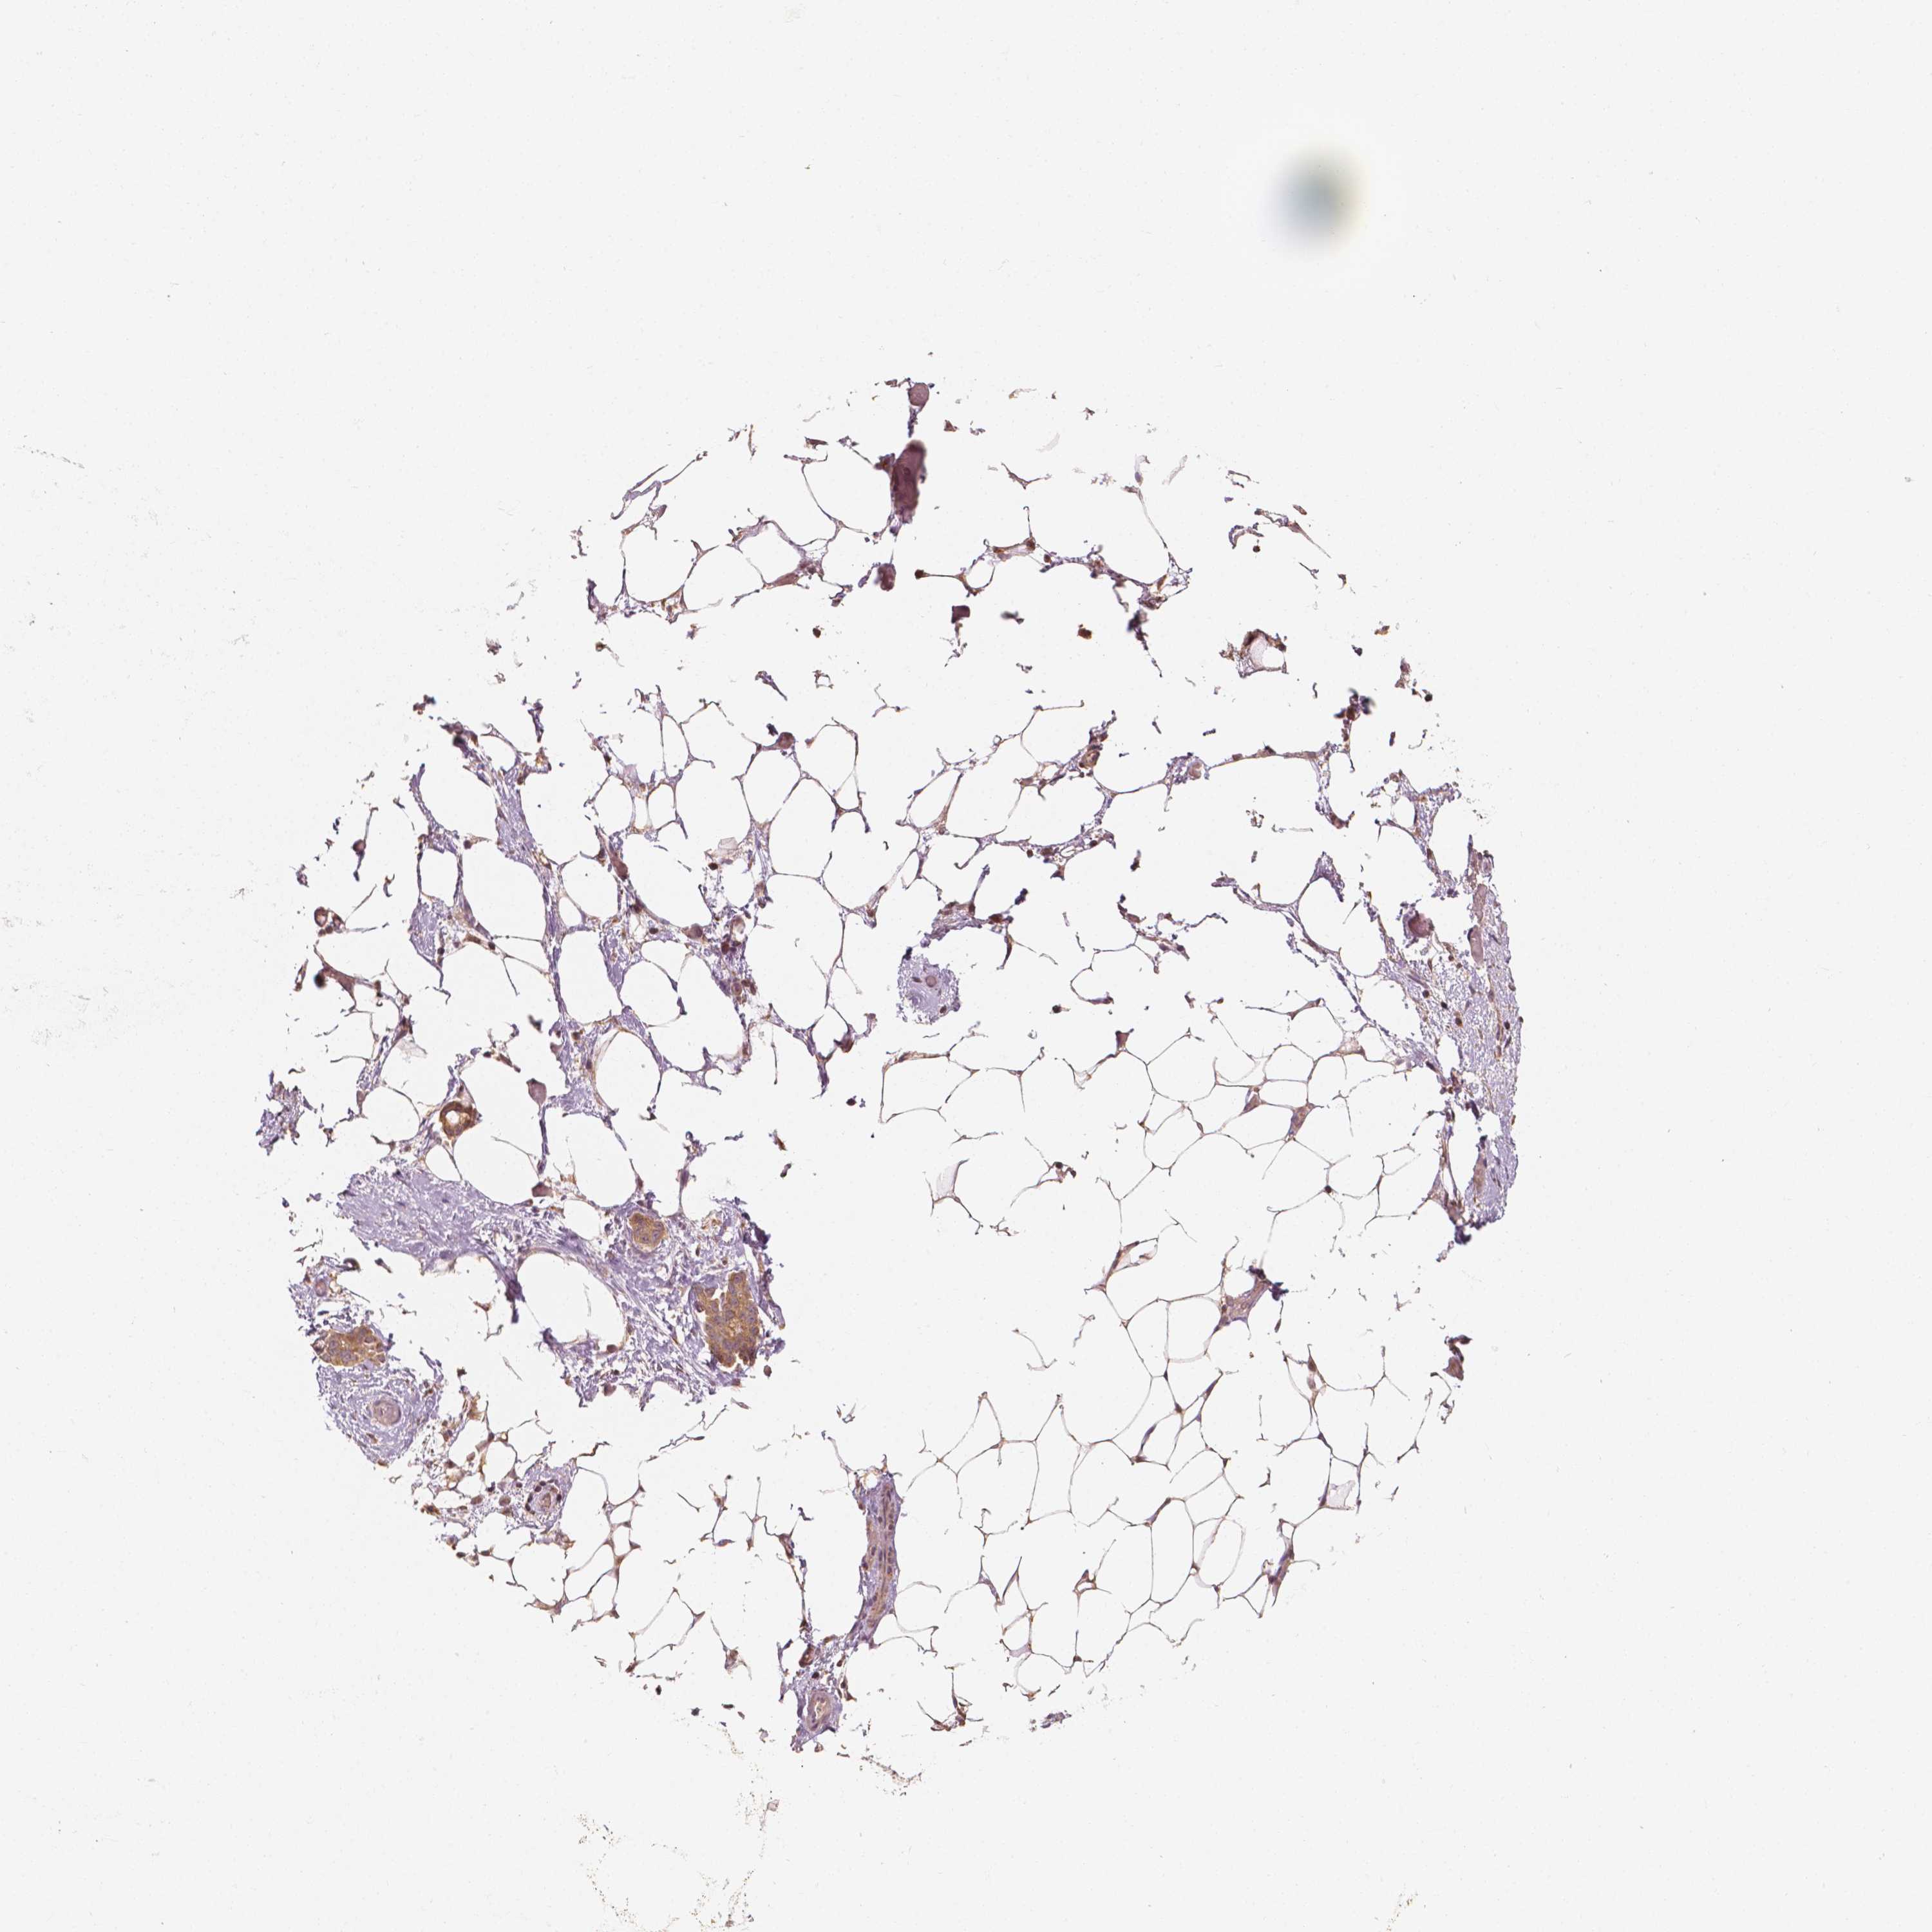

OVARIAN CANCER - Protein expressioni

A mouse-over function shows sample information and annotation data. Click on an image to view it in a full screen mode. Samples can be filtered based on level of antibody staining by selecting one or several of the following categories: high, medium, low and not detected. The assay and annotation is described here.

Note that samples used for immunohistochemistry by the Human Protein Atlas do not correspond to samples in the TCGA dataset.

Antibody stainingi

Antibody staining in the annotated cell types in the current human tissue is reported as not detected, low, medium, or high, based on conventional immunohistochemistry profiling in selected tissues. This score is based on the combination of the staining intensity and fraction of stained cells.

Each image is clickable and will lead to virtual microscopy that enables deeper exploration of all samples and also displays staining intensity scores, fraction scores and subcellular localization as well as patient and tissue information for each sample.

Antibody HPA024361

Antibody HPA064939

Cystadenocarcinoma, serous, NOS

Carcinoma, endometroid

Cystadenocarcinoma, mucinous, NOS

Carcinoma, NOS